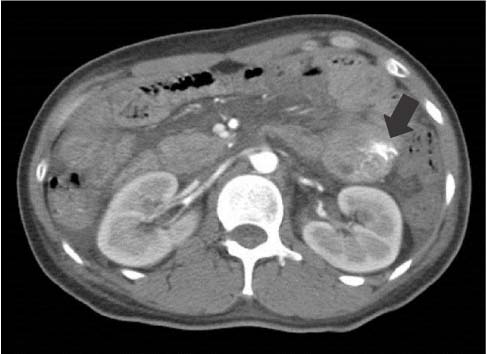

Fig. 1

Abdominal computed tomography finding. It shows extravasation of contrast agent with 1.5 cm sized filling detect (black arrow). It allows assessment of active bleeding in proximal jejunal loop with small mass.

Fig. 1 Abdominal computed tomography finding. It shows extravasation of contrast agent with 1.5 cm sized filling detect (black arrow). It allows assessment of active bleeding in proximal jejunal loop with small mass.